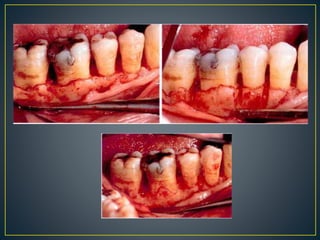

Craters and root trunk types

- Craters : shallow – 1-2mm

moderate : 3-4mm

deep : >5mm

- Amt of buccal bone removed – base of crater to root

trunk

- Root trunk : short, average & long

- Avg. 1.5 – 2mm CEJ to marginal bone (Orban, Wentz)

Ochsenbien 1986